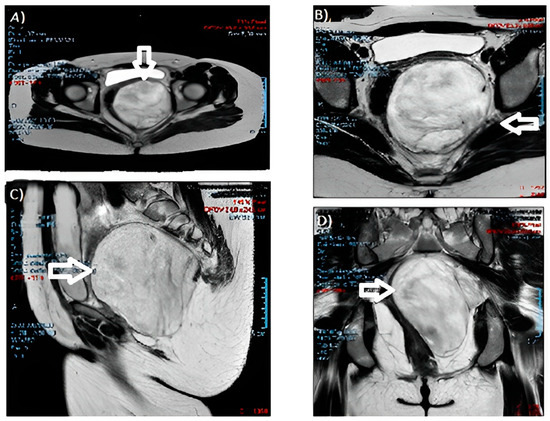

Aggressive Angiomyxoma of the Vulva: Which Is the Best Management Strategy? Description of a Case Report and Review of Literature of the Last Ten Years

by Ferdinando Antonio Gulino, Marianna Gulisano, Carla Ettore, Alexandra Giorlandino, Emanuele Russo and Giuseppe Ettore

J. Clin. Med. 2023, 12(5), 1726; https://doi.org/10.3390/jcm12051726 - 21 Feb 2023

Background: Aggressive angiomyxoma is a rare mesenchymal tumour of the genital tract with a high incidence in women of reproductive age. The aim of our work is to understand which is the best management strategy for this condition, starting from the description of a rare case report up to the performance of a narrative review of the literature. Methods: We report a case of a 46-year-old woman who came to our attention because of the growth of a 10-centimetre pedunculated, non-soft, non-tender mass of the left labium majus. She underwent surgical excision, and the histologic diagnosis was aggressive angiomyxoma. Due to a lack of tumour-free margins, radicalization surgery was carried out after three months. A review of the literature of the last ten years was performed following the PRISMA statement on MEDLINE (PubMed). We obtained data from twenty-five studies describing thirty-three cases. Results: Aggressive angiomyxoma is characterized by a high recurrence rate of between 36 and 72% after surgery. There is no universal consensus about hormonal therapy, and most studies (85%) describe surgical excision followed by only clinical and radiological follow-up. Conclusion: Wide surgical excision is the gold-standard treatment for aggressive angiomyxoma, succeeded by either clinical or radiological (ultrasound or MRI) follow-up. Full article

Figure 1